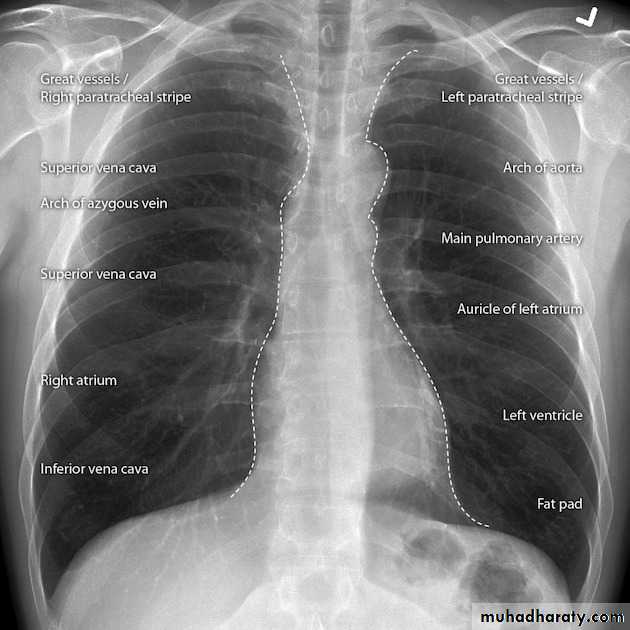

Approach to chest x ray